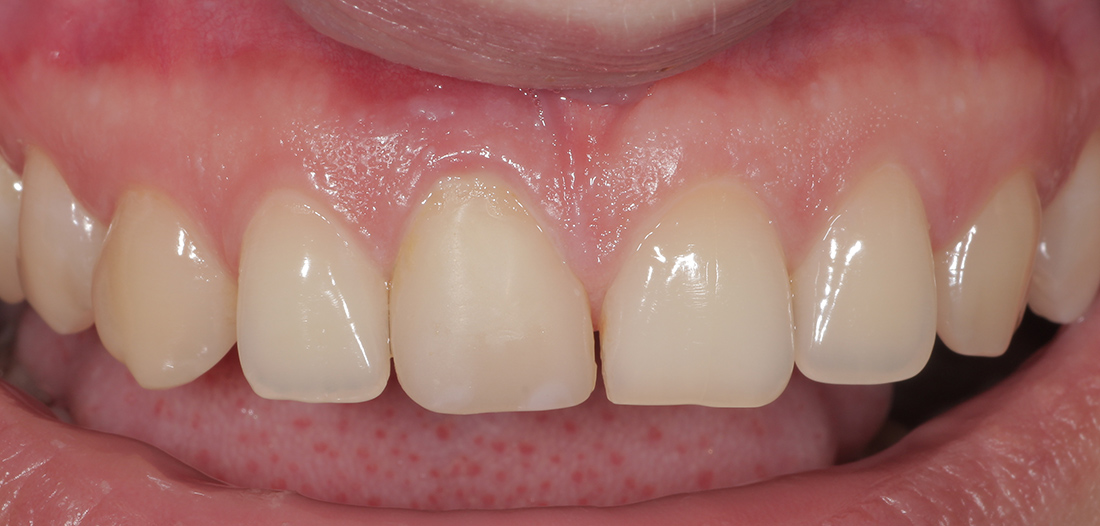

Исходная ситуация

Пациентка П., 26 лет. Обратилась с жалобами на подвижность и боли в области верхнего центрального резца. При клиническом и рентгенографическом обследовании выявлена внутриканальная резорбция корня, поперечный перелом и разрушение наружной костной стенки.